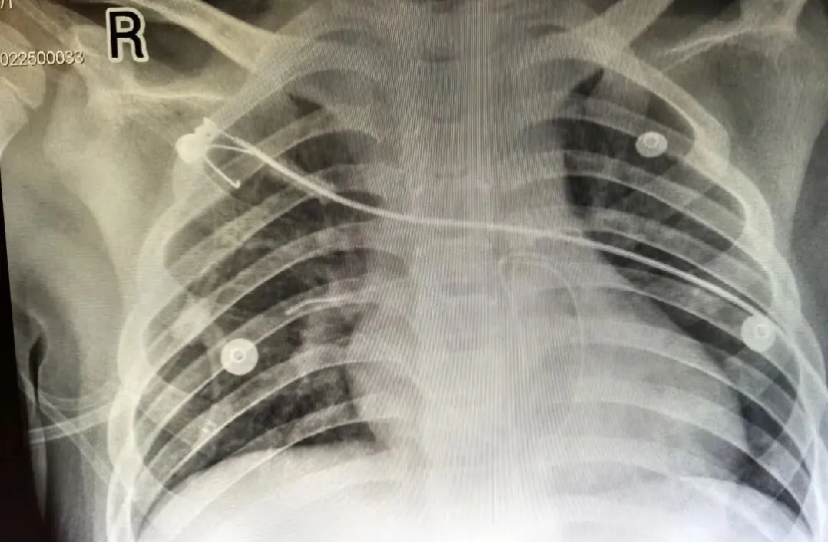

床旁超声、心电图、胸片同步展开,精准“锁定”断裂导管的位置:近端卡在右心室流出道,远端漂至右肺动脉,中段竟绕成环状,盘踞在左肺动脉起始部。需尽快手术取出。

(术前导管远端处于右肺动脉部位)